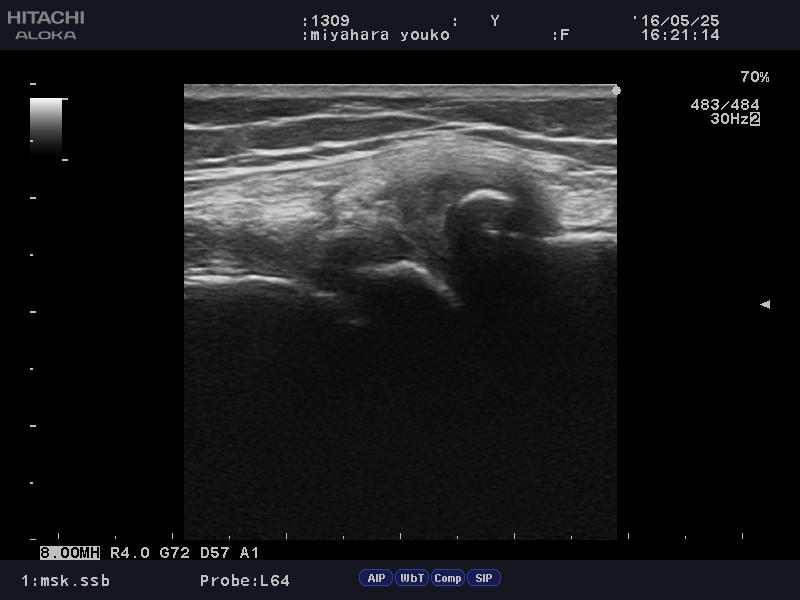

アイスホッケー ゴールキーパーで他人に膝の上に乗られ「膝の半月板」痛められた方。

lateral collateral ligament2.jpglateral collateral ligament.JPG